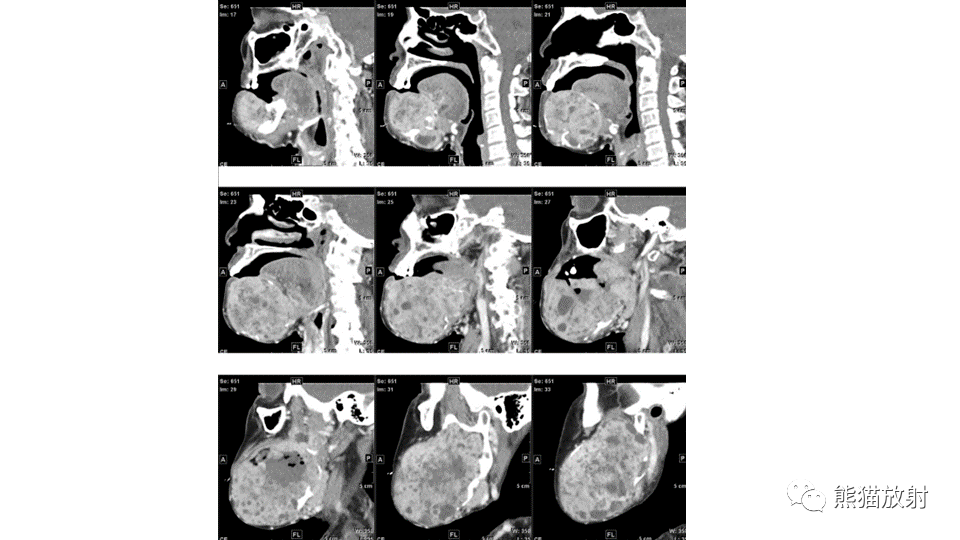

【病例】下颌骨成釉细胞瘤2例CT-8

【病例】下颌骨成釉细胞瘤2例CT-9

【病例】下颌骨成釉细胞瘤2例CT-10

【病例】下颌骨成釉细胞瘤2例CT-11

【病例】下颌骨成釉细胞瘤2例CT-12